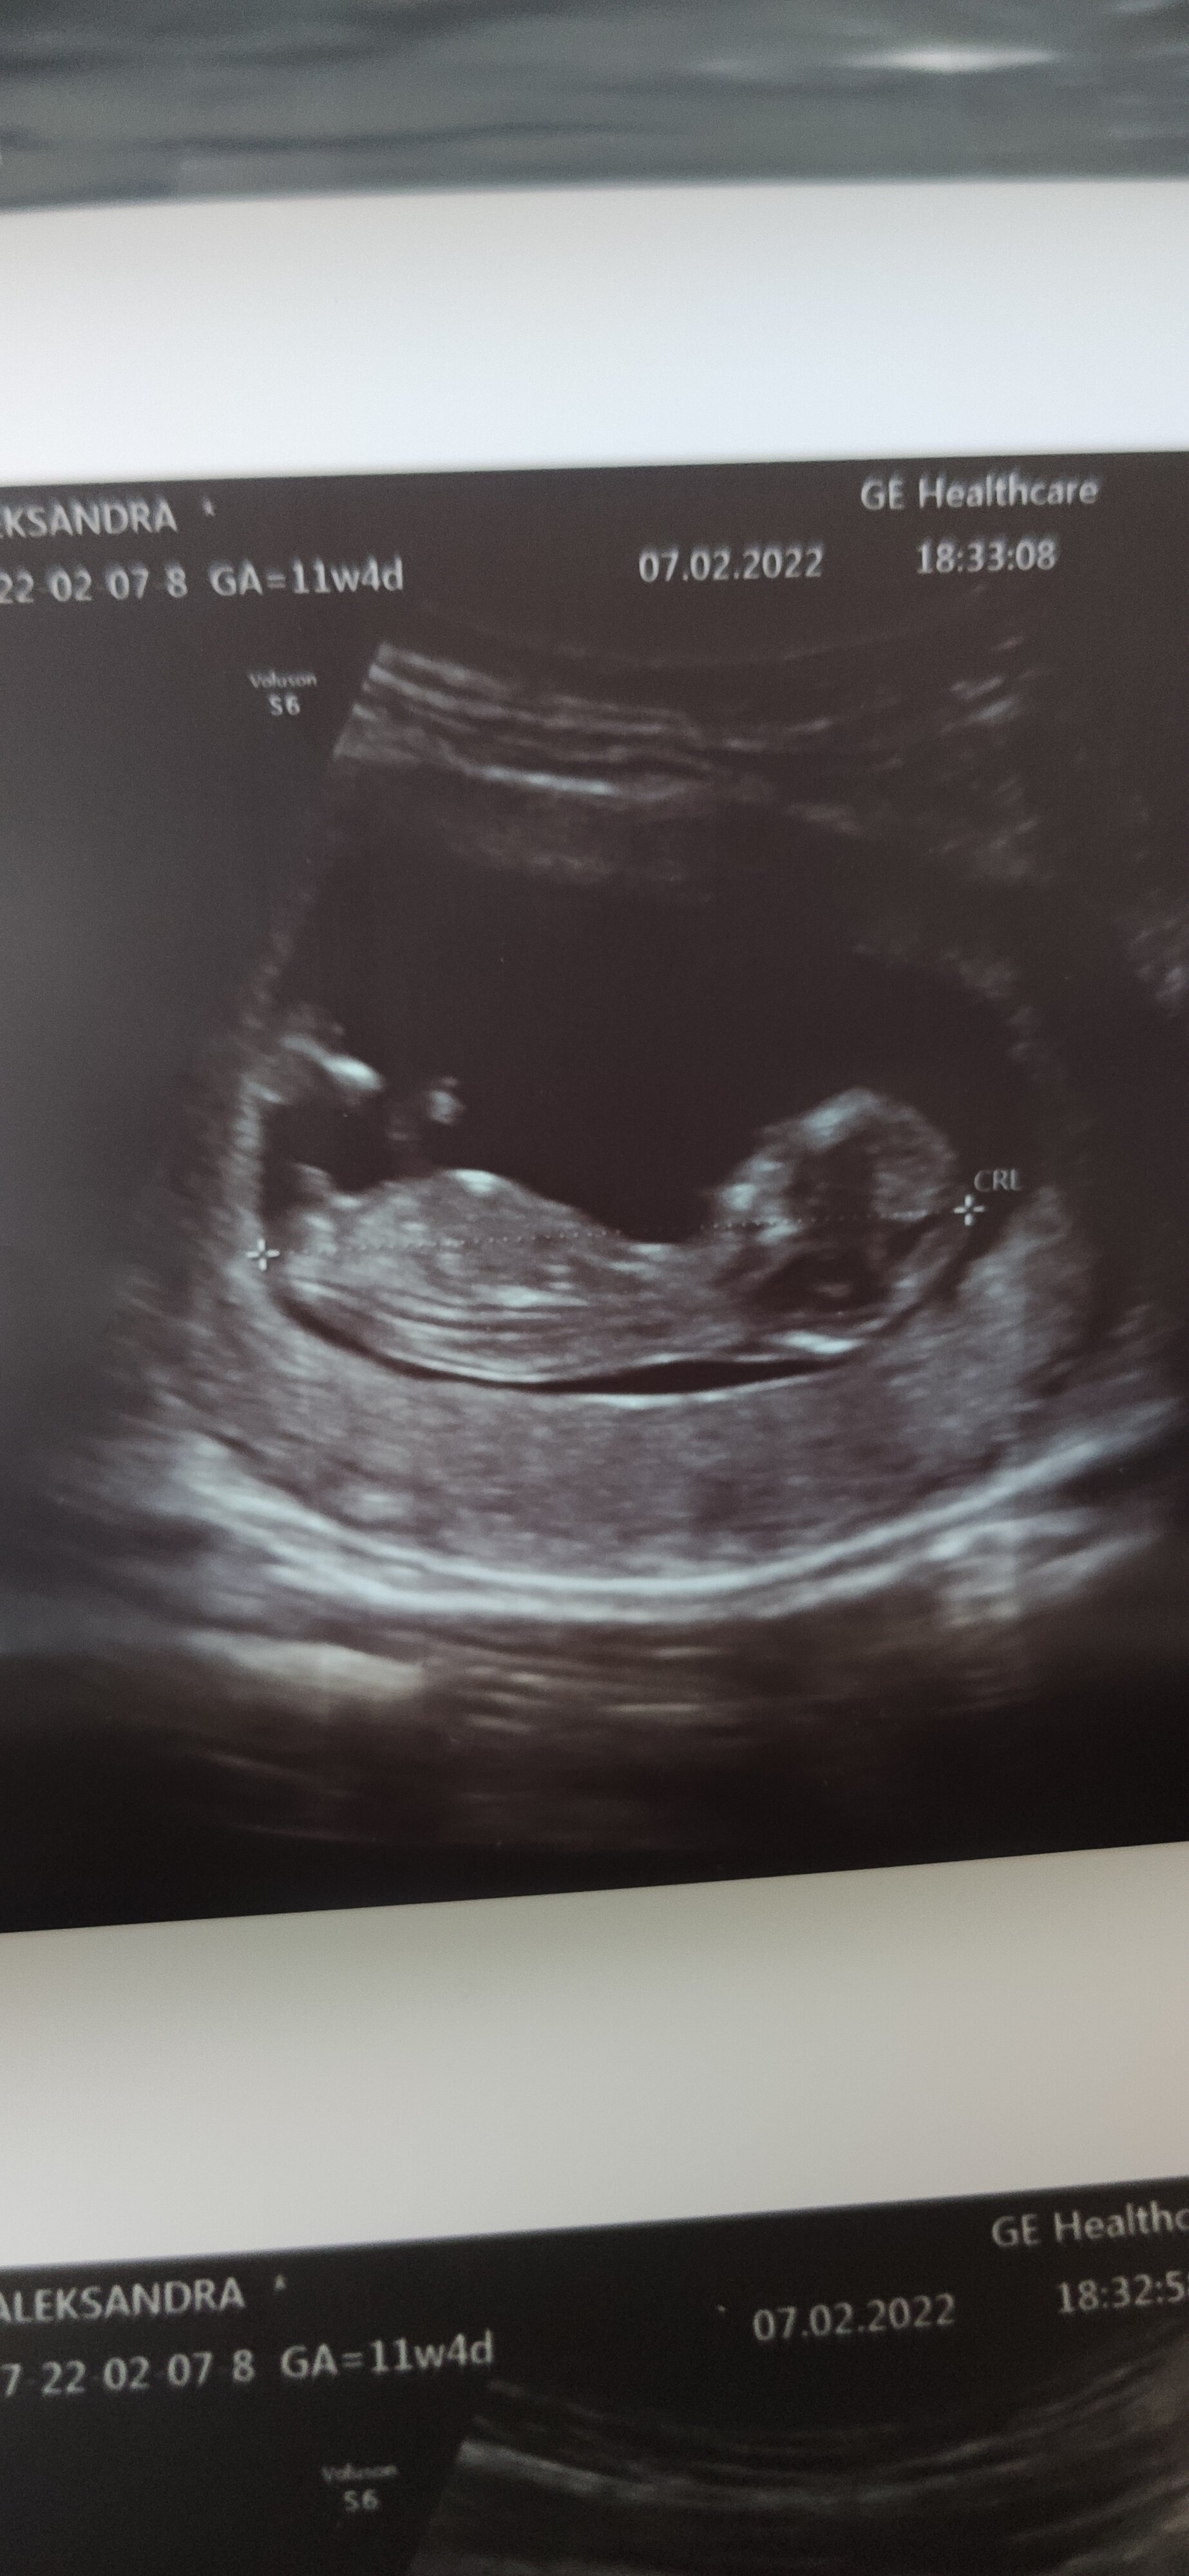

Ooo , ja obstawiam chłopca@Alexa95 Moim zdaniem dziewczynka. Ale na tym etapie to jeszcze wszystko podobnie wygląda. Jakby się dobrze przyjrzeć widać 3 kreseczki charakterystyczne dla dziewczynki.

U chłopca to w zasadzie trzecią nogę widać - tak dość nieproporcjonalnie to wygląda

Ale to wiesz - takie gdybanie - na ten moment masz szanse 50:50.

Płeć poznasz na badaniach połówkowych. Także wątpię, by na wizycie za tydzień było widać coś więcej.

Ja bym się nie nastawiała.